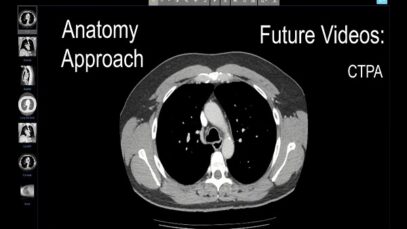

●High resolution computed tomography (HRCT, also called thin-section CT scanning) provides more detail than either chest radiography or conventional CT scanning, with an overall sensitivity of 95 percent and a specificity approaching 100 percent. Compared to chest radiography, HRCT can more accurately assess the pattern and distribution of diffuse lung disease, which may be beneficial […]